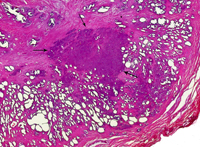

Aunque en la próstata existen varios tipos de células, es en las células glandulares, las responsables de la secreción que se produce durante la eyaculación, donde se originan la mayor parte de los cánceres prostáticos (95%) . Es el llamado adenocarcinoma de la próstata.